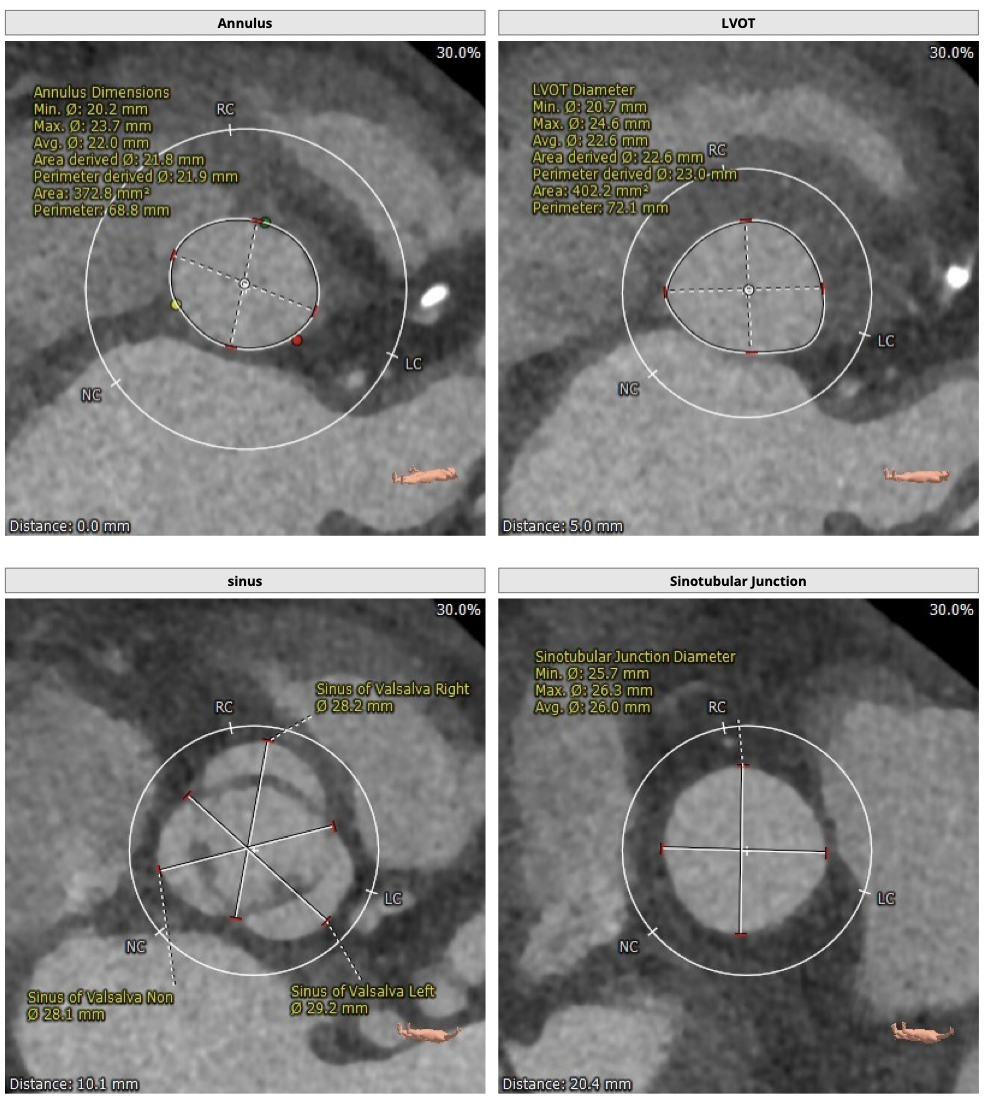

超声提示:主动脉瓣重度狭窄伴中度关闭不全,主动脉瓣口面积:0.8cm2主动脉向前速度:418cm/s,左房增大(40mm),左室肥厚伴舒张功能减退,少量心包积液,EF:64%。

CT检查

②主动脉根部钙化较轻,瓣叶肥厚,各交界缘不同程度粘连,瓣膜释放后具有瓣周漏风险;

③左冠高度不高,且瓣叶冗长,达冠脉开口层面,且冠脉存在狭窄,存在冠脉阻塞的风险;

确保冠脉安全,拟采取PCI+TAVR一站式手术策略,因患者右侧股动脉钙化严重、入路狭窄,拟采取无鞘法从右股动脉穿刺入路,选用20mm球囊预扩、L23号VenusA-Valve瓣膜、采用VenusA-Plus输送系统确保瓣膜的精确释放,瓣膜释放后结合造影和超声情况,决定是否后扩。